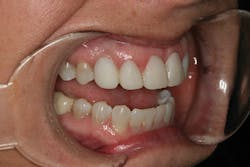

A 32-year-old white female presented for a cosmetic consultation. The patient reported that during her teenage years she had received orthodontic treatment to move her permanent maxillary canines mesially into the spaces that should have been occupied by her congenitally missing lateral incisors. She stated that her dentist, orthodontist, and oral surgeon had decided to place endosseous implants in the canine spaces due to the greater availability of bone in comparison to the bone available in the lateral positions (figure 1). As she grew older, she had become increasingly dissatisfied with the appearance of her smile and was seeking a more updated and esthetic solution (figure 2).

Figure 2